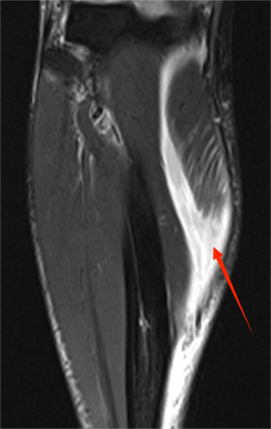

△踢足球之后的小腿肌肉拉伤